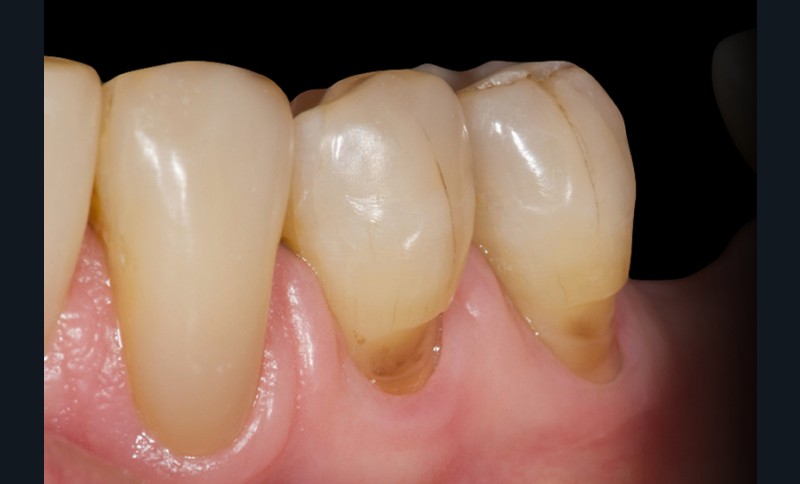

Les lésions cervicales non carieuses (LCNC ; Non-Carious Cervical Lesions, NCCL en anglais) sont des états pathologiques caractérisés par la perte de structure dentaire au niveau de la jonction amélo-cementaire qui ne sont pas liés à la carie dentaire [8] (fig. 1).

Les LCNC sont presque exclusivement situées sur les faces vestibulaires des dents, rarement sur les faces linguales et proximales. Plusieurs études ont montré qu’elles sont plus marquées sur les incisives, les canines et les prémolaires et qu’elles sont plus fréquentes sur le maxillaire qu’à la mandibule [7, 11].

En général, les LCNC varient…